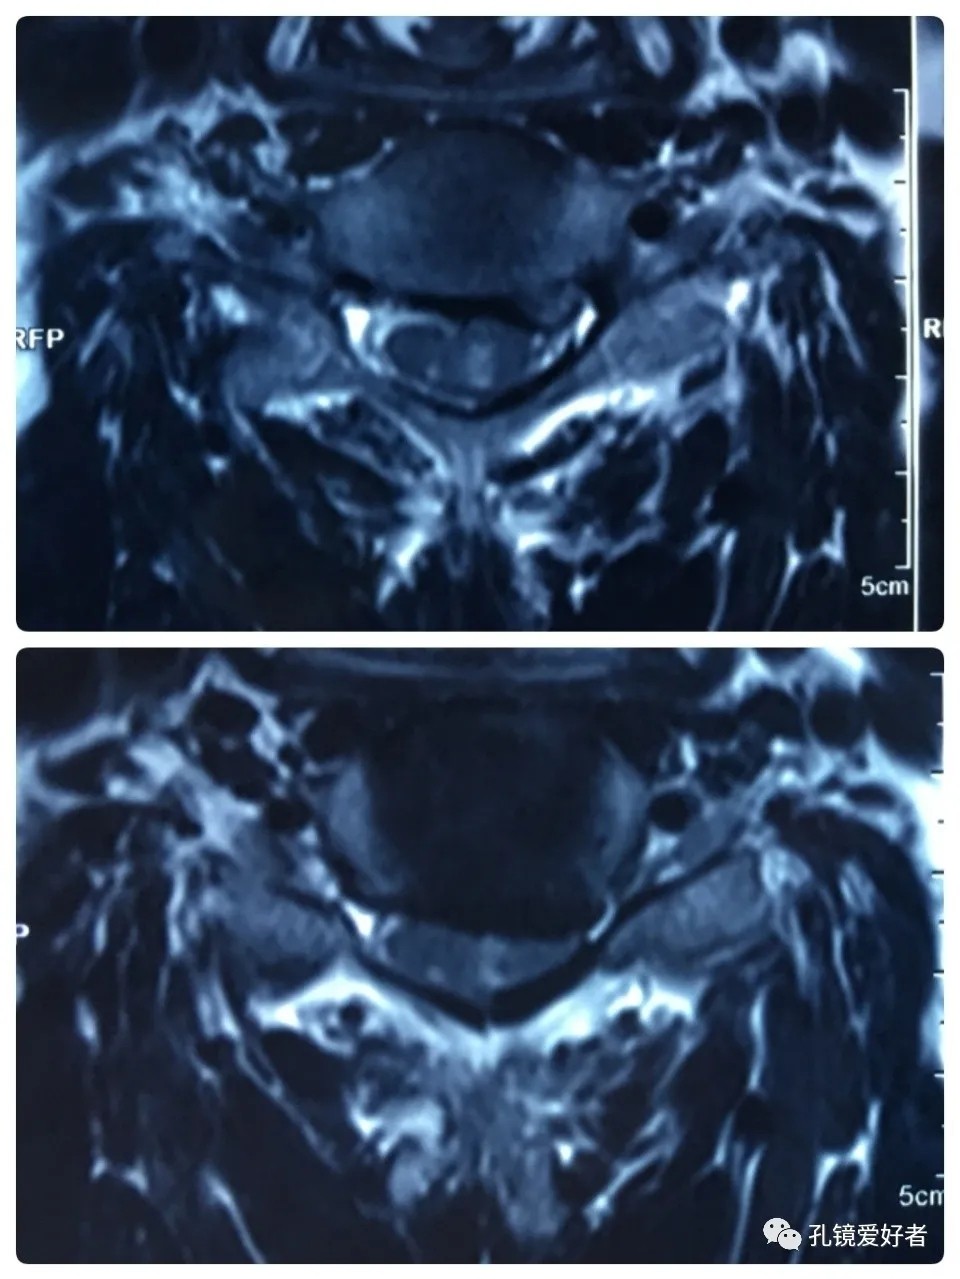

Plain MRI Scan

Then let's look at MRI.

The MRI shows that the cervical stenosis is on C3-4, C5-6 and C6-7. Considering the patient's clinical symptoms, C5-6 and C6-7 are the main affected segments. So it’s advised that the patient undergo posterior cervical open-door laminoplasty. According to the patient, he had visited many hospitals before and received similar proposals of diagnosis and treatment- posterior cervical open-door laminoplasty. The reason he came to our hospital was that he wanted his surgery could be performed in a minimally invasive way. After considerable preoperative discussion with my colleagues and the patient, we decided to perform the minimally invasive endoscopic decompression for C5-6 and C6-7 double-segment stenosis through posterior approach (with the Delta system).